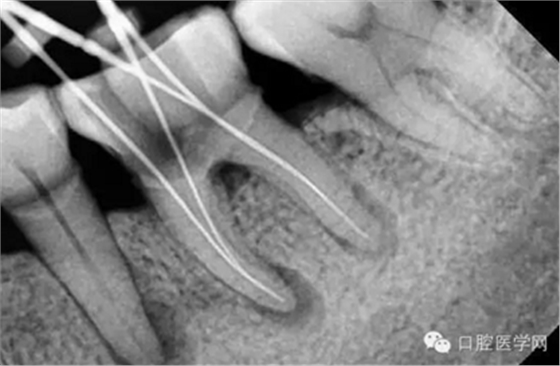

特殊情況可以插針拍片確定工作長度(一般我比較相信根測)

試尖(檢查是否恰填)

根充(從術(shù)后X光片可以看出根管充填完整,專業(yè)上叫恰充)